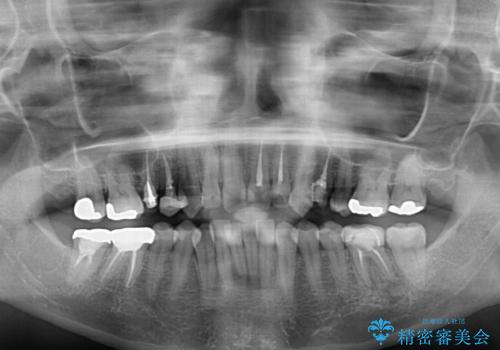

- 前歯のデコボコと奥歯の虫歯を気にして来院された患者様です。

主に下顎歯列全体の後方移動とIPR(歯と歯の間を削る)によってデコボコが解消するように設計し、インビザラインにより治療を行うこととしました。

矯正治療後半に下顎左右奥歯をセラミッククラウンにて補綴し、その後インビザラインによる歯列の仕上げを行うこととしました。

下顎前歯の叢生が速やかに改善されたため、1年3か月で治療を終えることができました。